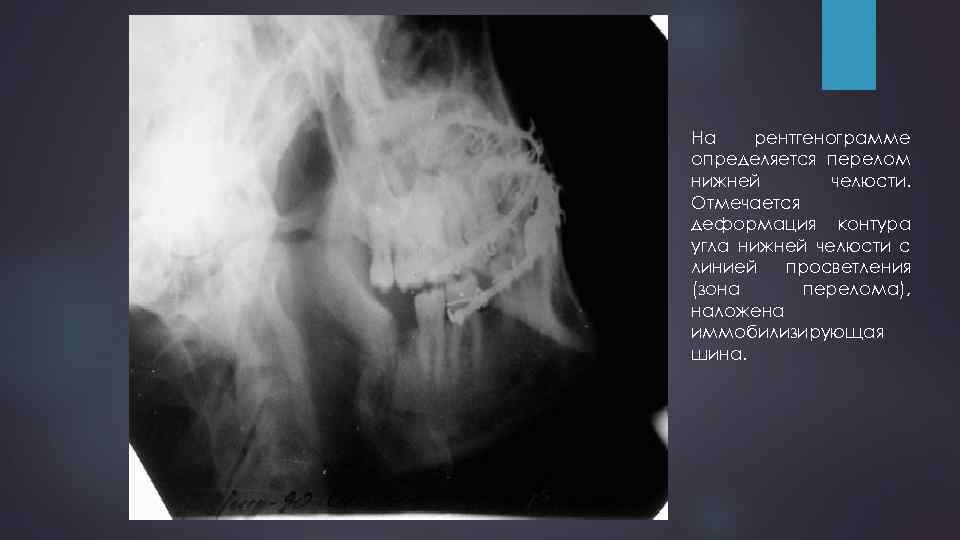

Перелом нижней челюсти 46

На рентгенограмме определяется перелом нижней челюсти. Отмечается деформация контура угла нижней челюсти с линией просветления (зона перелома), наложена иммобилизирующая шина.